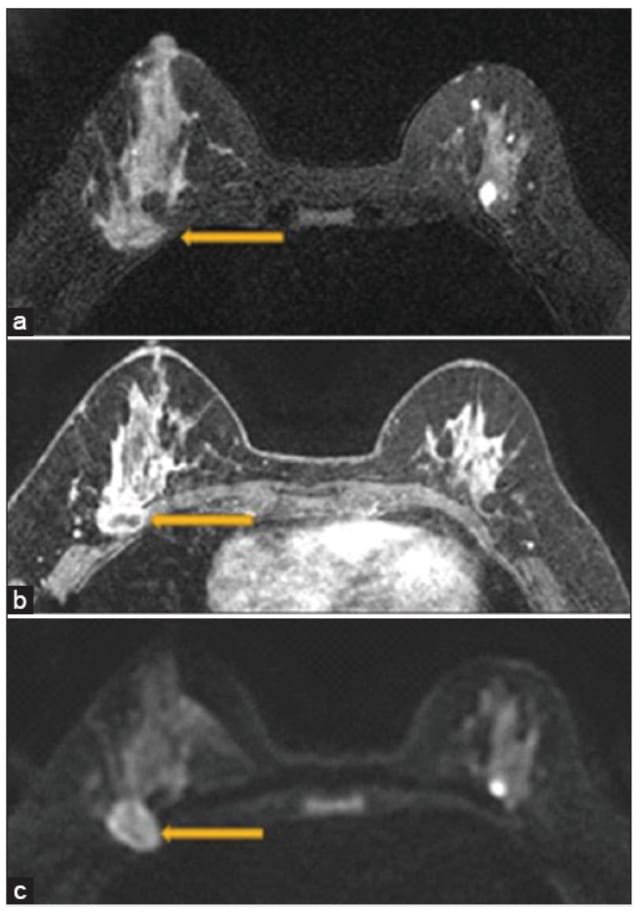

Gambar. Seorang wanita 47 tahun dengan karsinoma invasif payudara kanan yang terbukti dengan biopsi. Pencitraan resonansi magnetik payudara menunjukkan infiltrasi ke otot pectoralis (panah) pada T2 (a), infiltrasi ke otot pectoralis (panah) pada T1+Kontras (b), dan gambaran restricted ( infiltrasi ) ke otot pectoralis (panah) pada DWI (c ). Patologi bedah menunjukkan bukti keterlibatan otot rangka.13

MRI dapat mengevaluasi infiltrasi lesi ke aspek posterior dari payudara, menilai ukuran tumor secara 3 dimensi dan mengevaluasi lesi multifocal atau multicenter pada payudara. Dengan mengetahui ada / tidaknya infiltrasi tumor payudara klinisi dapat menentukan mangemen terapi lebih lanjut.13